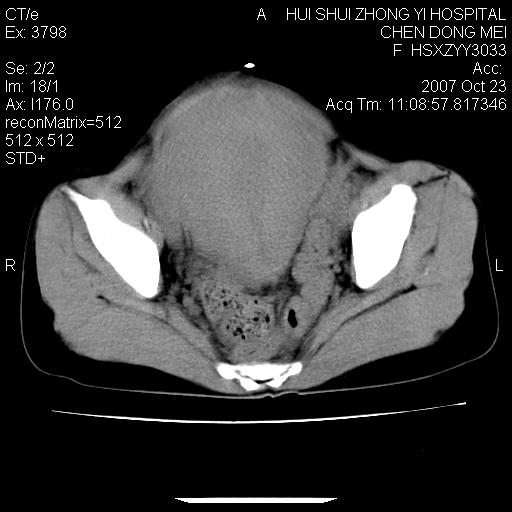

标题: CT10156:女.43岁,发现中下腹部包都块2年 [打印本页]

标题: CT10156:女.43岁,发现中下腹部包都块2年

发现中下腹部包都块2年。2年来月经不规律。

腹腔巨大软组织密度影,边缘光滑,包膜完整,内囊变坏死。腹膜后及盆腔内淋巴结肿大。结合病史考虑卵巢癌可能性大。

病变巨大,呈囊实性改变,包膜较厚且完整,内见分膈,周围脏器明显受压移位,病变与左侧附件关系密切,考虑来源左侧附件的囊腺瘤,不除外癌变可能;畸胎瘤可能性较小。

病变巨大,呈囊实性改变,包膜较厚且完整,内见分膈,周围脏器明显受压移位,病变与左侧附件关系密切,考虑来源左侧附件的囊腺瘤,盆腔内见肿大淋巴结,不除外癌变可能。

病变巨大,呈囊实性改变,包膜较厚且完整,内见分膈,周围脏器明显受压移位,病变与左侧附件关系密切,考虑来源左侧附件的囊腺瘤,不除外癌变可能